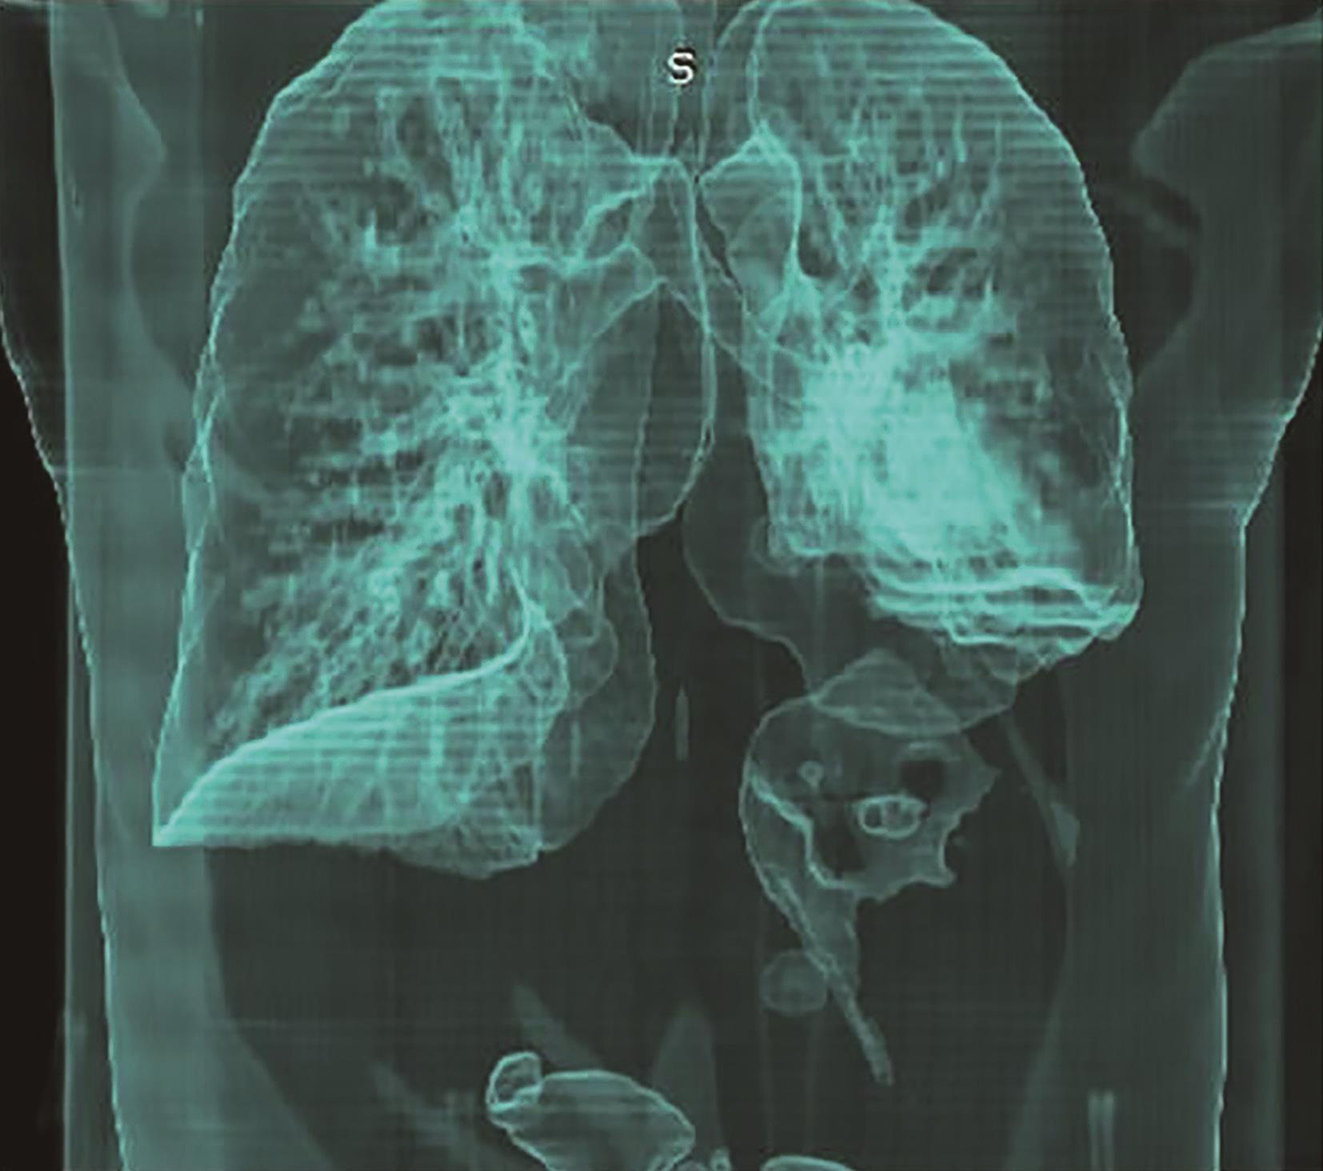

全腹部增强CT:左上腹软组织肿块,大小约16.4cm×12.3cm,考虑胃底大弯侧来源GIST伴左侧膈肌侵犯可能性大,需与淋巴瘤、神经鞘瘤、平滑肌瘤等其他胃黏膜下少见肿瘤鉴别(图1、图2)。

图2首诊CT三维重建示左侧膈肌侵犯可能性大